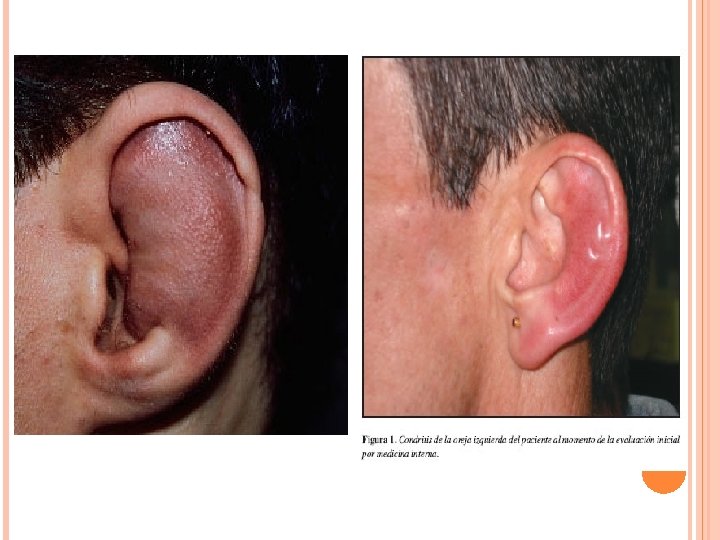

TRAUMATISMOS Por la rica vascularización conviene realizar una cuidadosa sutura, previo drenaje y antisepsia. Complicacion mas frecuente es el otohematoma. El cartílago se nutre por imbibición del pericondrio, un golpe tangencial sobre la piel del pabellón que esta adherida al pericondrio, puede separar a este del cartílago, formando una colección hemática que impide su nutrición llevándolo a la necrosis con la consiguiente deformación estética. El paciente presenta una tumefacción roja violácea del pabellón auricular. Se debe realizar una incisión evacuadora con la colocación de un drenaje y vendaje compresivo, prescribiéndose antibióticos, antiinflamatorio. Si hay arrancamiento total de la oreja se debe traer el fragmento en hielo para luego proceder a su reimplantación con cirugía microvascular.

HEMATOMA Es secundario a la ruptura de vasos entre el cartílago y el pericondrio, generalmente en la cara externa del pabellón. Generalmente secundarios a traumatismos (boxeadores), pero pueden ser espontáneos. Dejado evolucionar se puede producir la reabsorción del cartílago produciendo una deformación llamada oreja de "coliflor". Tratamiento Drenar el hematoma, si es pequeño con punción y si es grande con incisión. Posteriormente aplicar compresión con vendaje externo que adose la piel al cartílago subyacente.

Tratamiento Eliminar el material infectado que se encuentra en el canal mediante aspiración o con hisopos. Instilacion de gotas de antibiótico. Analgésicos como la codeína. Antibiótico via oral. Se deja que los furúnculos drenen por sí solos porque el hecho de abrirlos puede diseminar la infección. Pericondritis del pabellón auricular Es la inflamación del pericondrio que recubre el cartílago del pabellón auricular, suele estar producidad por Pseudomona aeruginosa. Por traumático, otohematona, cirugía, picadura de insecto. Pericondritis por erisipela es una enfermedad post streptococcica (Streptococo b hemolítico). Oreja aparece enrojecida, tumefacta y dolorosa. Si la infección progresa hay necrosis del cartílago. Tratamiento Consiste en la evacuación de la colección purulenta , vendaje compresivo y antibióticos.